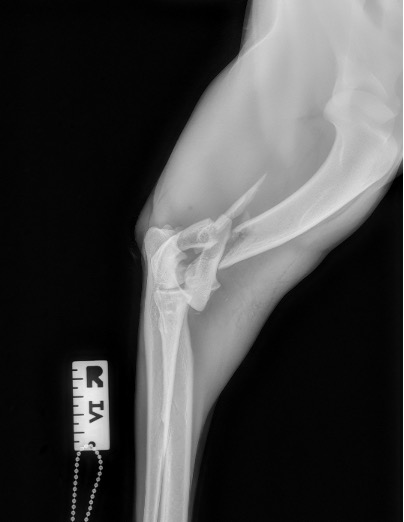

Exemple 1 :

Figure 1 : Pré-op

Exemple 2 :

Figure 4 : Pré-Op

Exemple 3 :

Figure 9 : Pré-Op